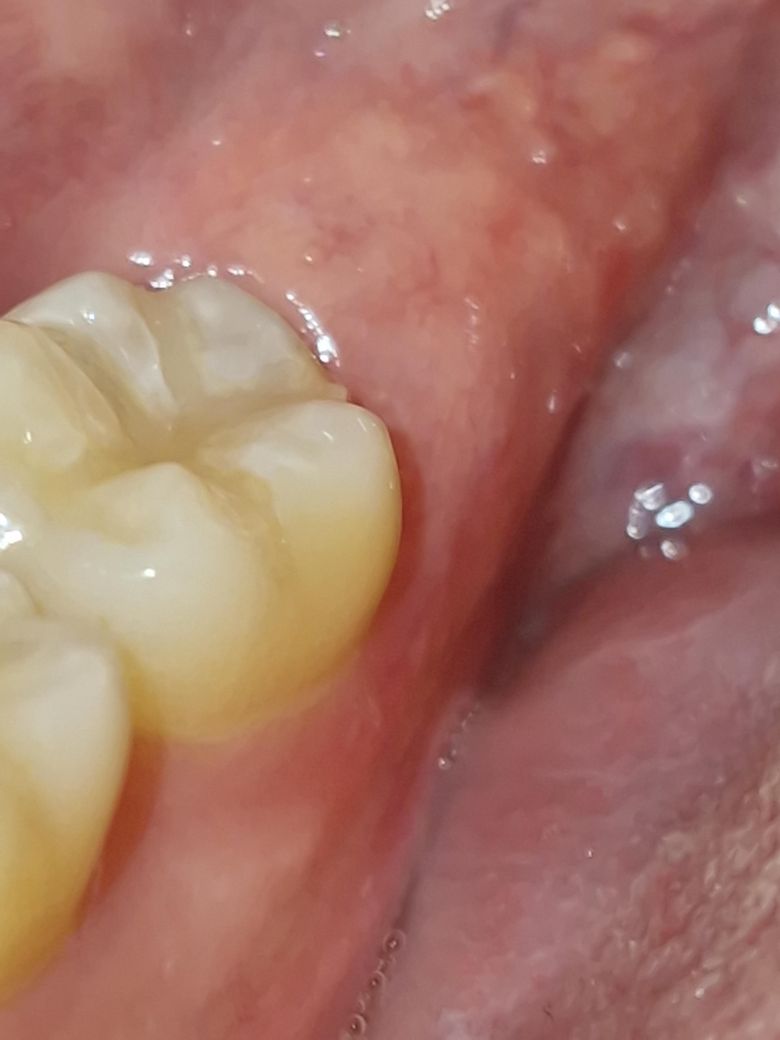

어금니 뒤쪽 잇몸이 내려간 것? 같아요

어금니 뒤 잇몸이 내려간 것 같아요. 다른 쪽 어금니에 비해 어금니 뒤쪽이 만져질 정도로요. 사랑니 때문인가요? 시간이 지나면 다시 원래대로 돌아올 수 있나요?

• 2번 째 사진